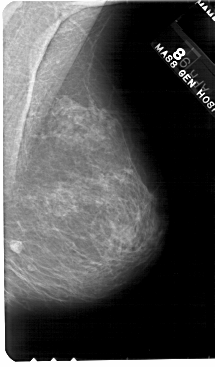

A_1562_1.RIGHT_MLO

RIGHT_MLO LINES 5491 PIXELS_PER_LINE 3211 BITS_PER_PIXEL 12 RESOLUTION 43.5 NON_OVERLAY